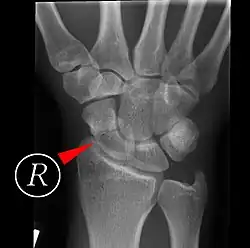

Trotzdem haben die klinischen Zeichen insgesamt eine geringe Spezifität, und auch Röntgenaufnahmen zeigen initial bei bis 40 % der Fälle keine Frakturlinie. Bei der Röntgendiagnostik erfolgen bei entsprechendem Verdacht vier Aufnahmen der Handwurzel einschließlich zweier Schrägaufnahmen („Kahnbein-Quartett“). Alternativ kann neben den zwei Standardaufnahmen des Handgelenks eine einzelne Aufnahme nach Stecher erfolgen, bei der die Hand zur Faust geballt und nach ulnar abduziert gehalten wird. Ist ein Bruch trotz klinischen Verdachts nicht sicher festzustellen, erfolgt zur Diagnosesicherung in der Regel eine Computertomographie, oder – insbesondere bei Kindern, bei denen Strahlenschutz eine noch größere Rolle spielt – eine Magnetresonanztomographie.